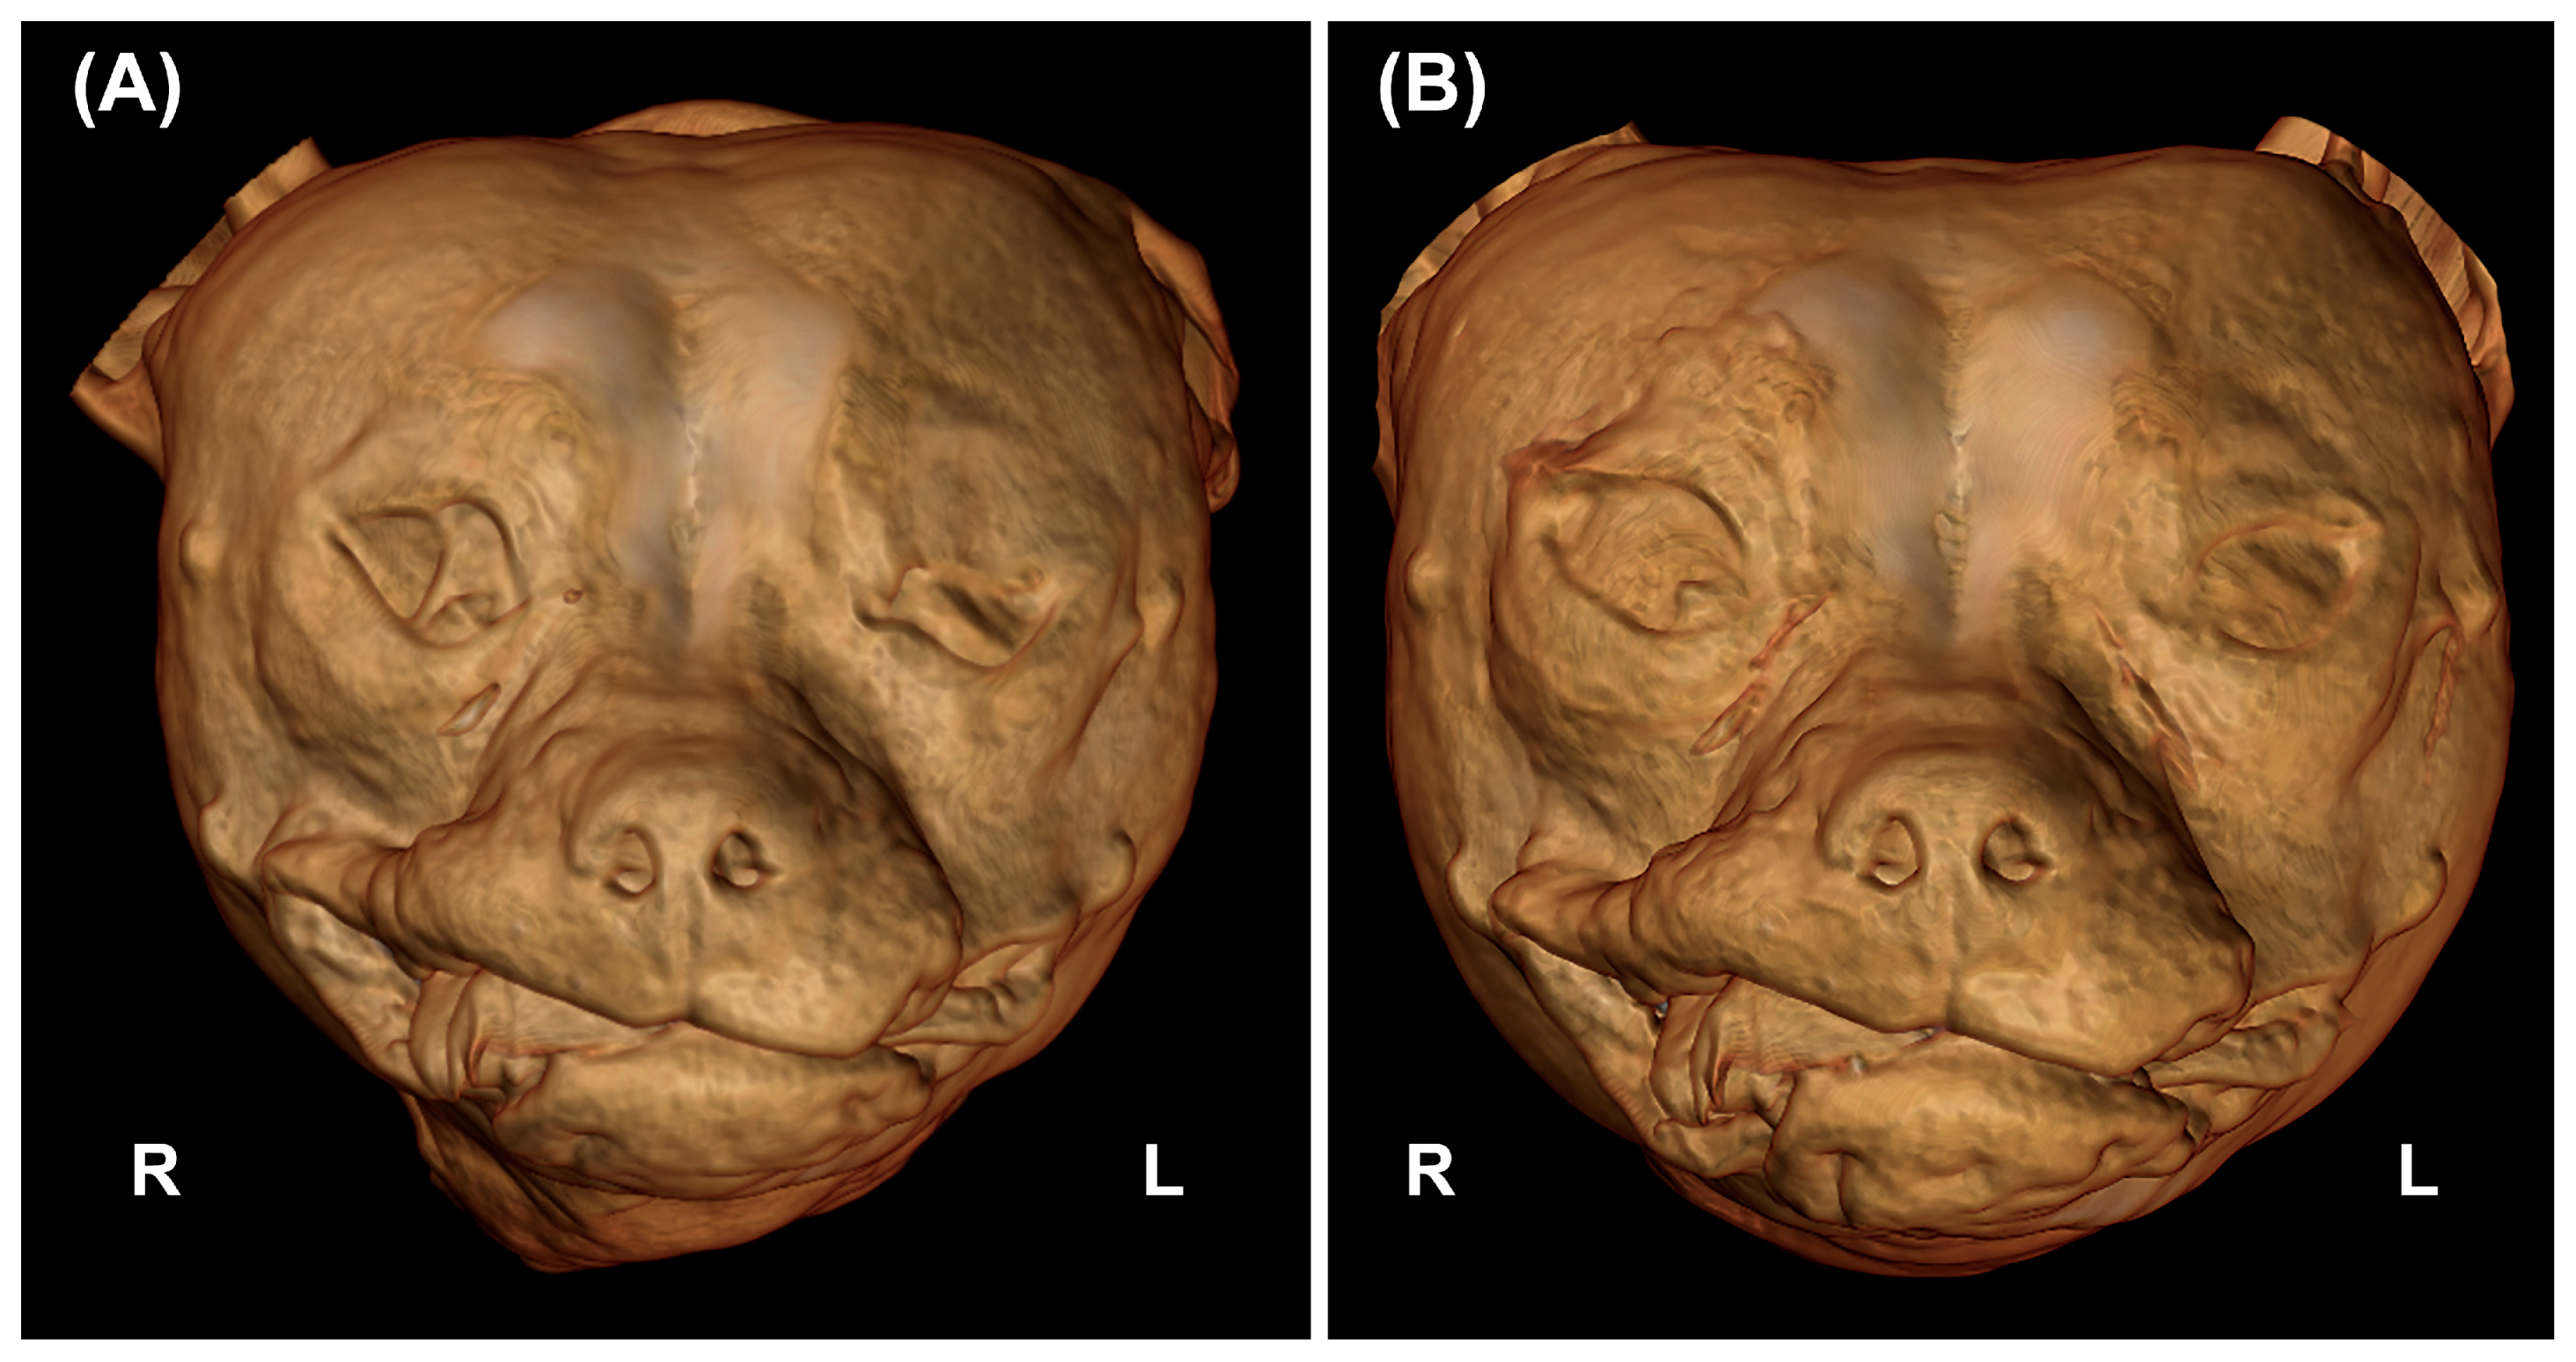

3.4. CT Images Findings

3.5. Statistical Results